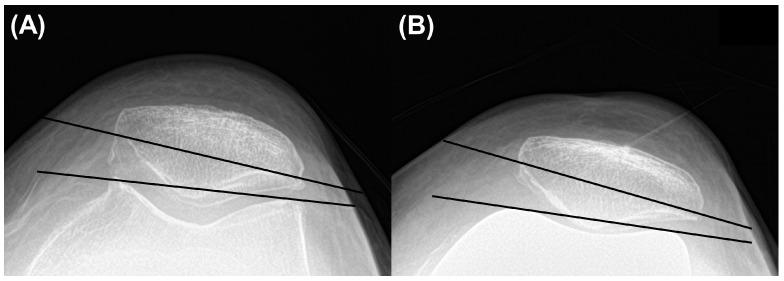

The purpose was to compare the clinical and radiographic outcomes between preoperative mild and severe varus deformity after total knee arthroplasty (TKA) with medial stabilizing technique (MST). We retrospectively analyzed 158 knees of 125 female patients with a 2-year follow-up who underwent mechanically aligned TKA with MST between April 2018 and February 2021. Patients were divided into two groups; the severe varus group was defined as one with preoperative hip-knee ankle (HKA) angle ≥ 15° and the mild varus group with HKA angle < 15°. Pre- and post-operative clinical outcomes (Western Ontario and McMaster University Osteoarthritis Index, Knee Society Knee Score) and radiographic outcomes (medial proximal tibial angle (MPTA), HKA angle, lateral distal femoral angle (LDFA), joint line distance, and femoral component rotation angle) were compared between the groups. Among the 158 knees analyzed, 131 and 27 were allocated to the mild and severe varus groups, respectively. Preoperative data showed that the MPTA (84.7° ± 2.8° vs. 80.7° ± 3.2°, < 0.001) was significantly less in the severe varus group. In postoperative data, clinical outcomes were not different between the groups. Joint line distance (18.4 mm ± 2.8 mm vs. 18.6 mm ± 2.7 mm, = 0.676) was also not significantly different. Femoral component rotation angle (-1.7° ± 1.0° vs. -1.0° ± 1.3°, = 0.018) was more externally rotated in the severe varus group. Severe varus group showed comparable clinical and radiographic outcomes to that of mild varus group after mechanically aligned TKA with MST.

目的是比较采用内侧稳定技术(MST)的全膝关节置换术(TKA)后术前轻度和重度内翻畸形之间的临床和影像学结果。我们回顾性分析了2018年4月至2021年2月期间接受MST机械对线TKA的125例女性患者的158个膝关节,随访2年。患者分为两组;重度内翻组定义为术前髋-膝-踝(HKA)角≥15°,轻度内翻组HKA角<15°。比较两组术前和术后的临床结果(西安大略和麦克马斯特大学骨关节炎指数、膝关节协会膝关节评分)和影像学结果(胫骨近端内侧角(MPTA)、HKA角、股骨远端外侧角(LDFA)、关节线距离和股骨假体旋转角)。在分析的158个膝关节中,分别有131个和27个被分配到轻度和重度内翻组。术前数据显示,重度内翻组的MPTA(84.7°±2.8°对80.7°±3.2°,<0.001)明显更小。术后数据显示,两组临床结果无差异。关节线距离(18.4 mm±2.8 mm对18.6 mm±2.7 mm,=0.676)也无显著差异。重度内翻组的股骨假体旋转角(-1.7°±1.0°对-1.0°±1.3°,=0.018)更向外旋转。在采用MST进行机械对线TKA后,重度内翻组的临床和影像学结果与轻度内翻组相当。